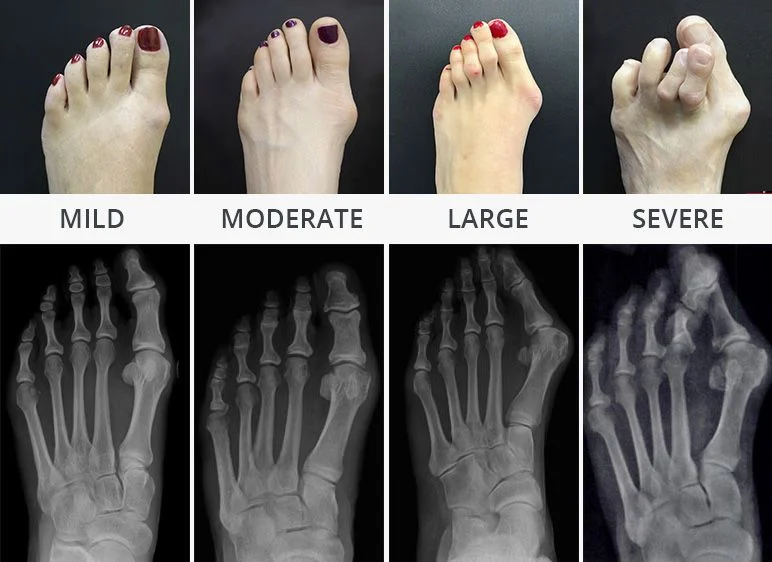

Bunions (Hallux Valgus) Deformity Stages

If symptoms of bunion is severe, surgery is the only effective treatment to relieve the pain. The most appropriate type of surgery depends on multiple factors, such as the extent of changes associated with bunion bump deformities as well as the bone changes and position of the bones in the foot. Our Podiatrists will explain the reasoning behind a particular decision in your specific case.